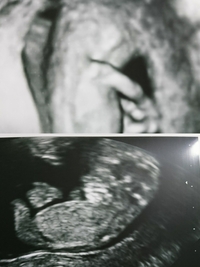

11週の時のエコーです 先生からは元気に動いてますね と言われただけ 妊娠 教えて Goo